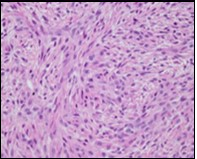

The neoplasm frequently infiltrates abutting skeletal muscle. Occasionally, tumefaction denominates hyper-cellular foci, tumour necrosis, cellular or nuclear atypia and mitotic figures, features which are characteristic of intermediate to high grade sarcoma. Localized tumour reoccurrence may be hyper-cellular with enhanced mitotic activity 4, 5. On ultrastructural examination, fibroblastic differentiation is exemplified 5. Figure 1, Figure 2, Figure 3, Figure 4, Figure 5, Figure 6, Figure 7, Figure 8.

Figure 3.Low grade fibromyxoid sarcoma demonstrating alternating fibrous and myxoid areas comprised of uniform spindle-shaped cells (11).